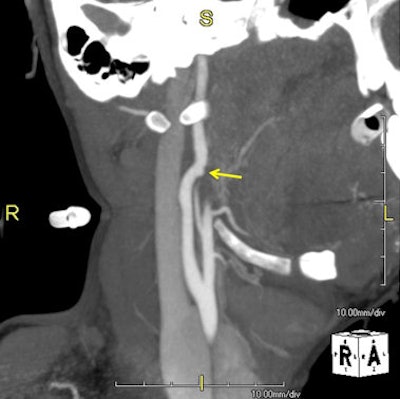

Top: 3D volume-rendered image of a patient following a submental shotgun wound. The yellow arrow indicates the trajectory of the gunshot wound and the red arrow encircles the right internal carotid artery (ICA) pseudoaneurysm. Bottom: Sagittal oblique maximum intensity projection (MIP) image demonstrates ICA pseudoaneurysm, indicated by the yellow arrow. All images courtesy of Dr. Scott Steenburg.